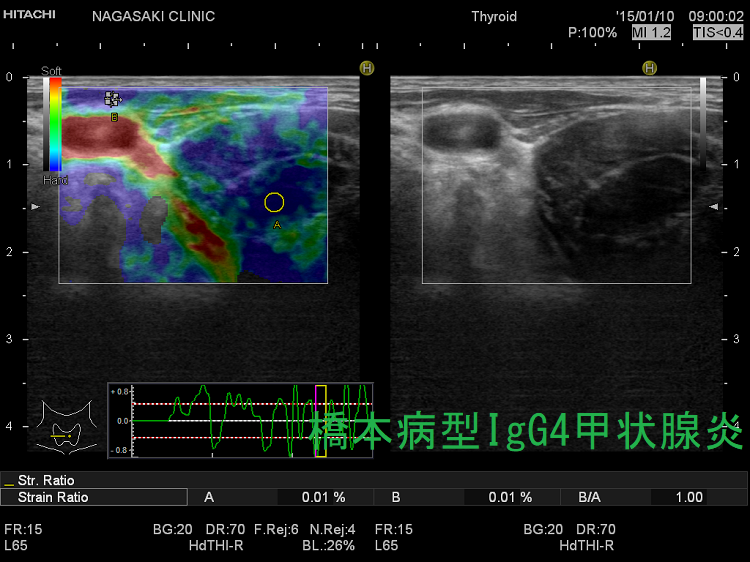

IgG4甲状腺炎(橋本病型IgG4甲状腺炎) 超音波(エコー)画像

橋本病の4.3%でIgG4高値(高ガンマグロブリン血症患者で多い)。IgG4甲状腺炎(橋本病型IgG4甲状腺炎)は急速進行型橋本病で甲状腺機能低下が速く①男性の比率が高い②抗甲状腺ペルオキシダーゼ抗体(TPO抗体)と抗サイログロブリン抗体(Tg抗体)価が高い③超音波エコー画像は巨大甲状腺腫、びまん性低エコー、肉芽腫性炎症による腫瘤形成、エラストグラフィーで硬い。IgG4関連疾患(IgG4-RD)の合併が少ない臓器特異的IgG4関連疾患。通常の橋本病と穿刺細胞診では鑑別不能、組織診(コア生検)で著明な線維化とIgG4免疫染色でIgG4産生形質細胞を確認。

- 超音波(エコー)画像では、巨大な甲状腺腫、内部びまん性低エコー、肉芽腫性炎症による腫瘤形成を認める

それ以前に、筆者の経験では線維化しているため硬くて針が通りません(ドライタップ)。結局、組織診(コア生検)でIgG4免疫染色するしかありません。